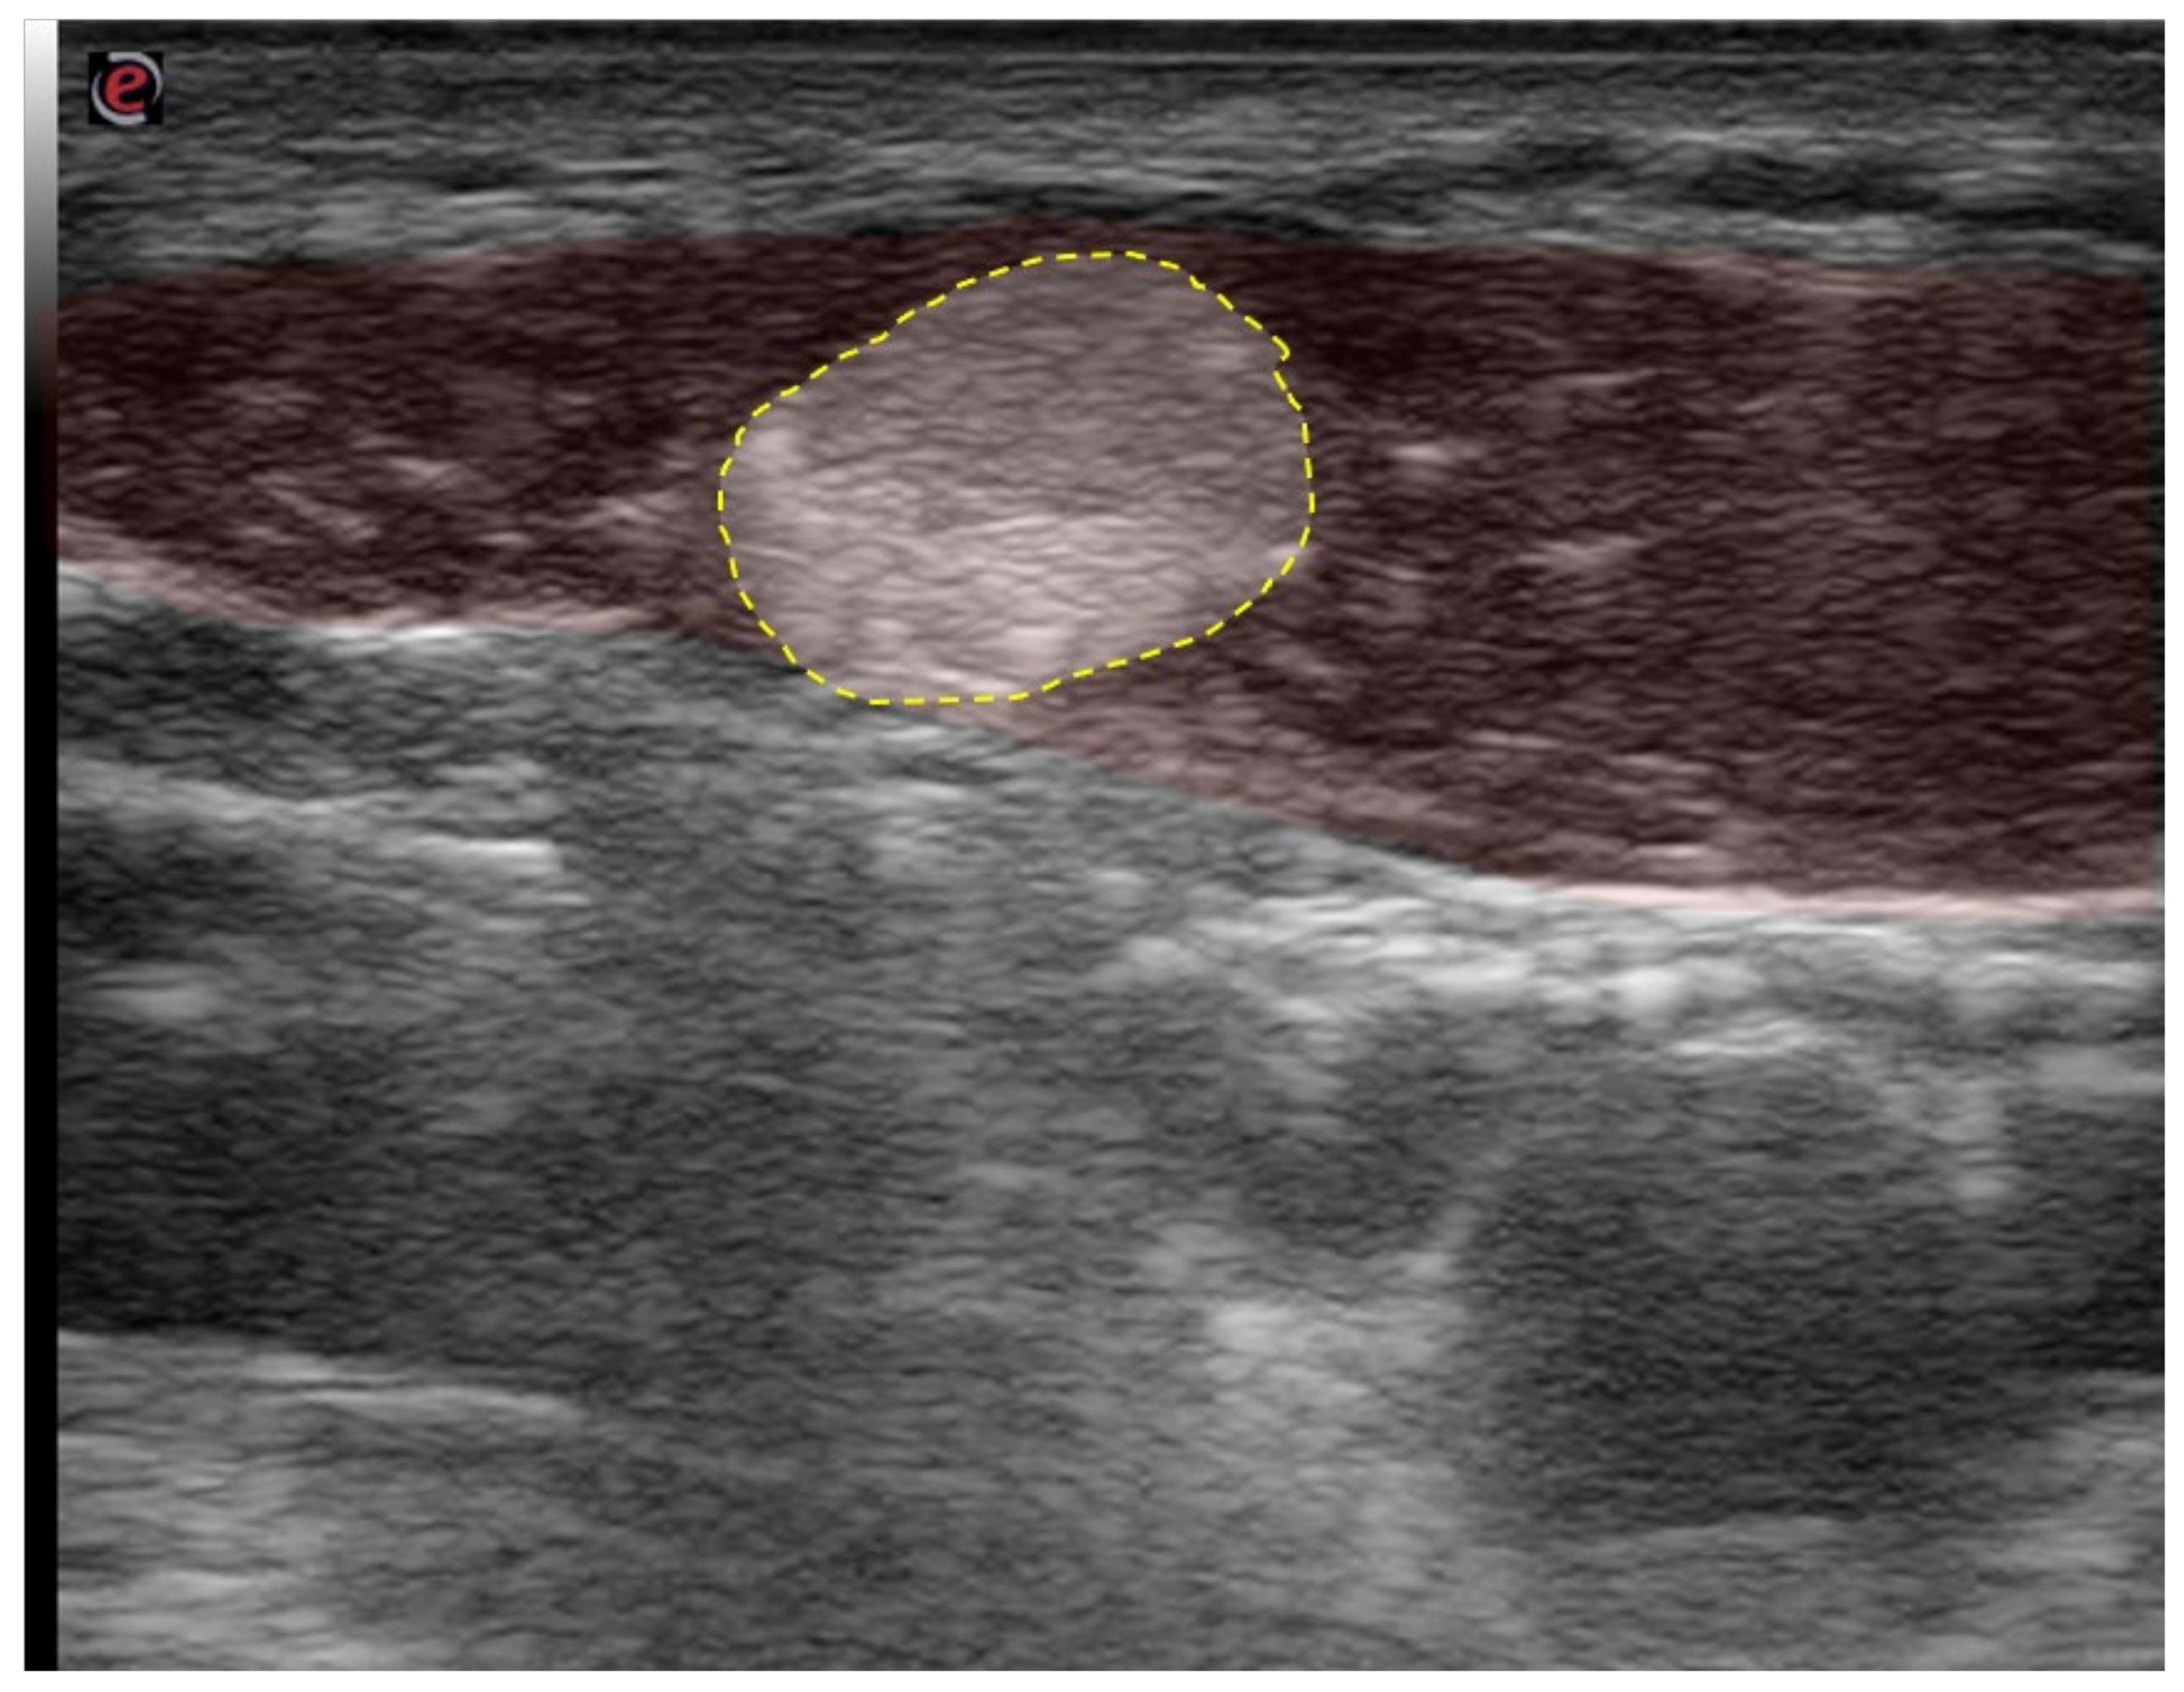

6.1. “Depth Matters”—Do Not Underestimate the 3rd Dimension

6.2. “Expect the Unexpected”—Variant Anatomy